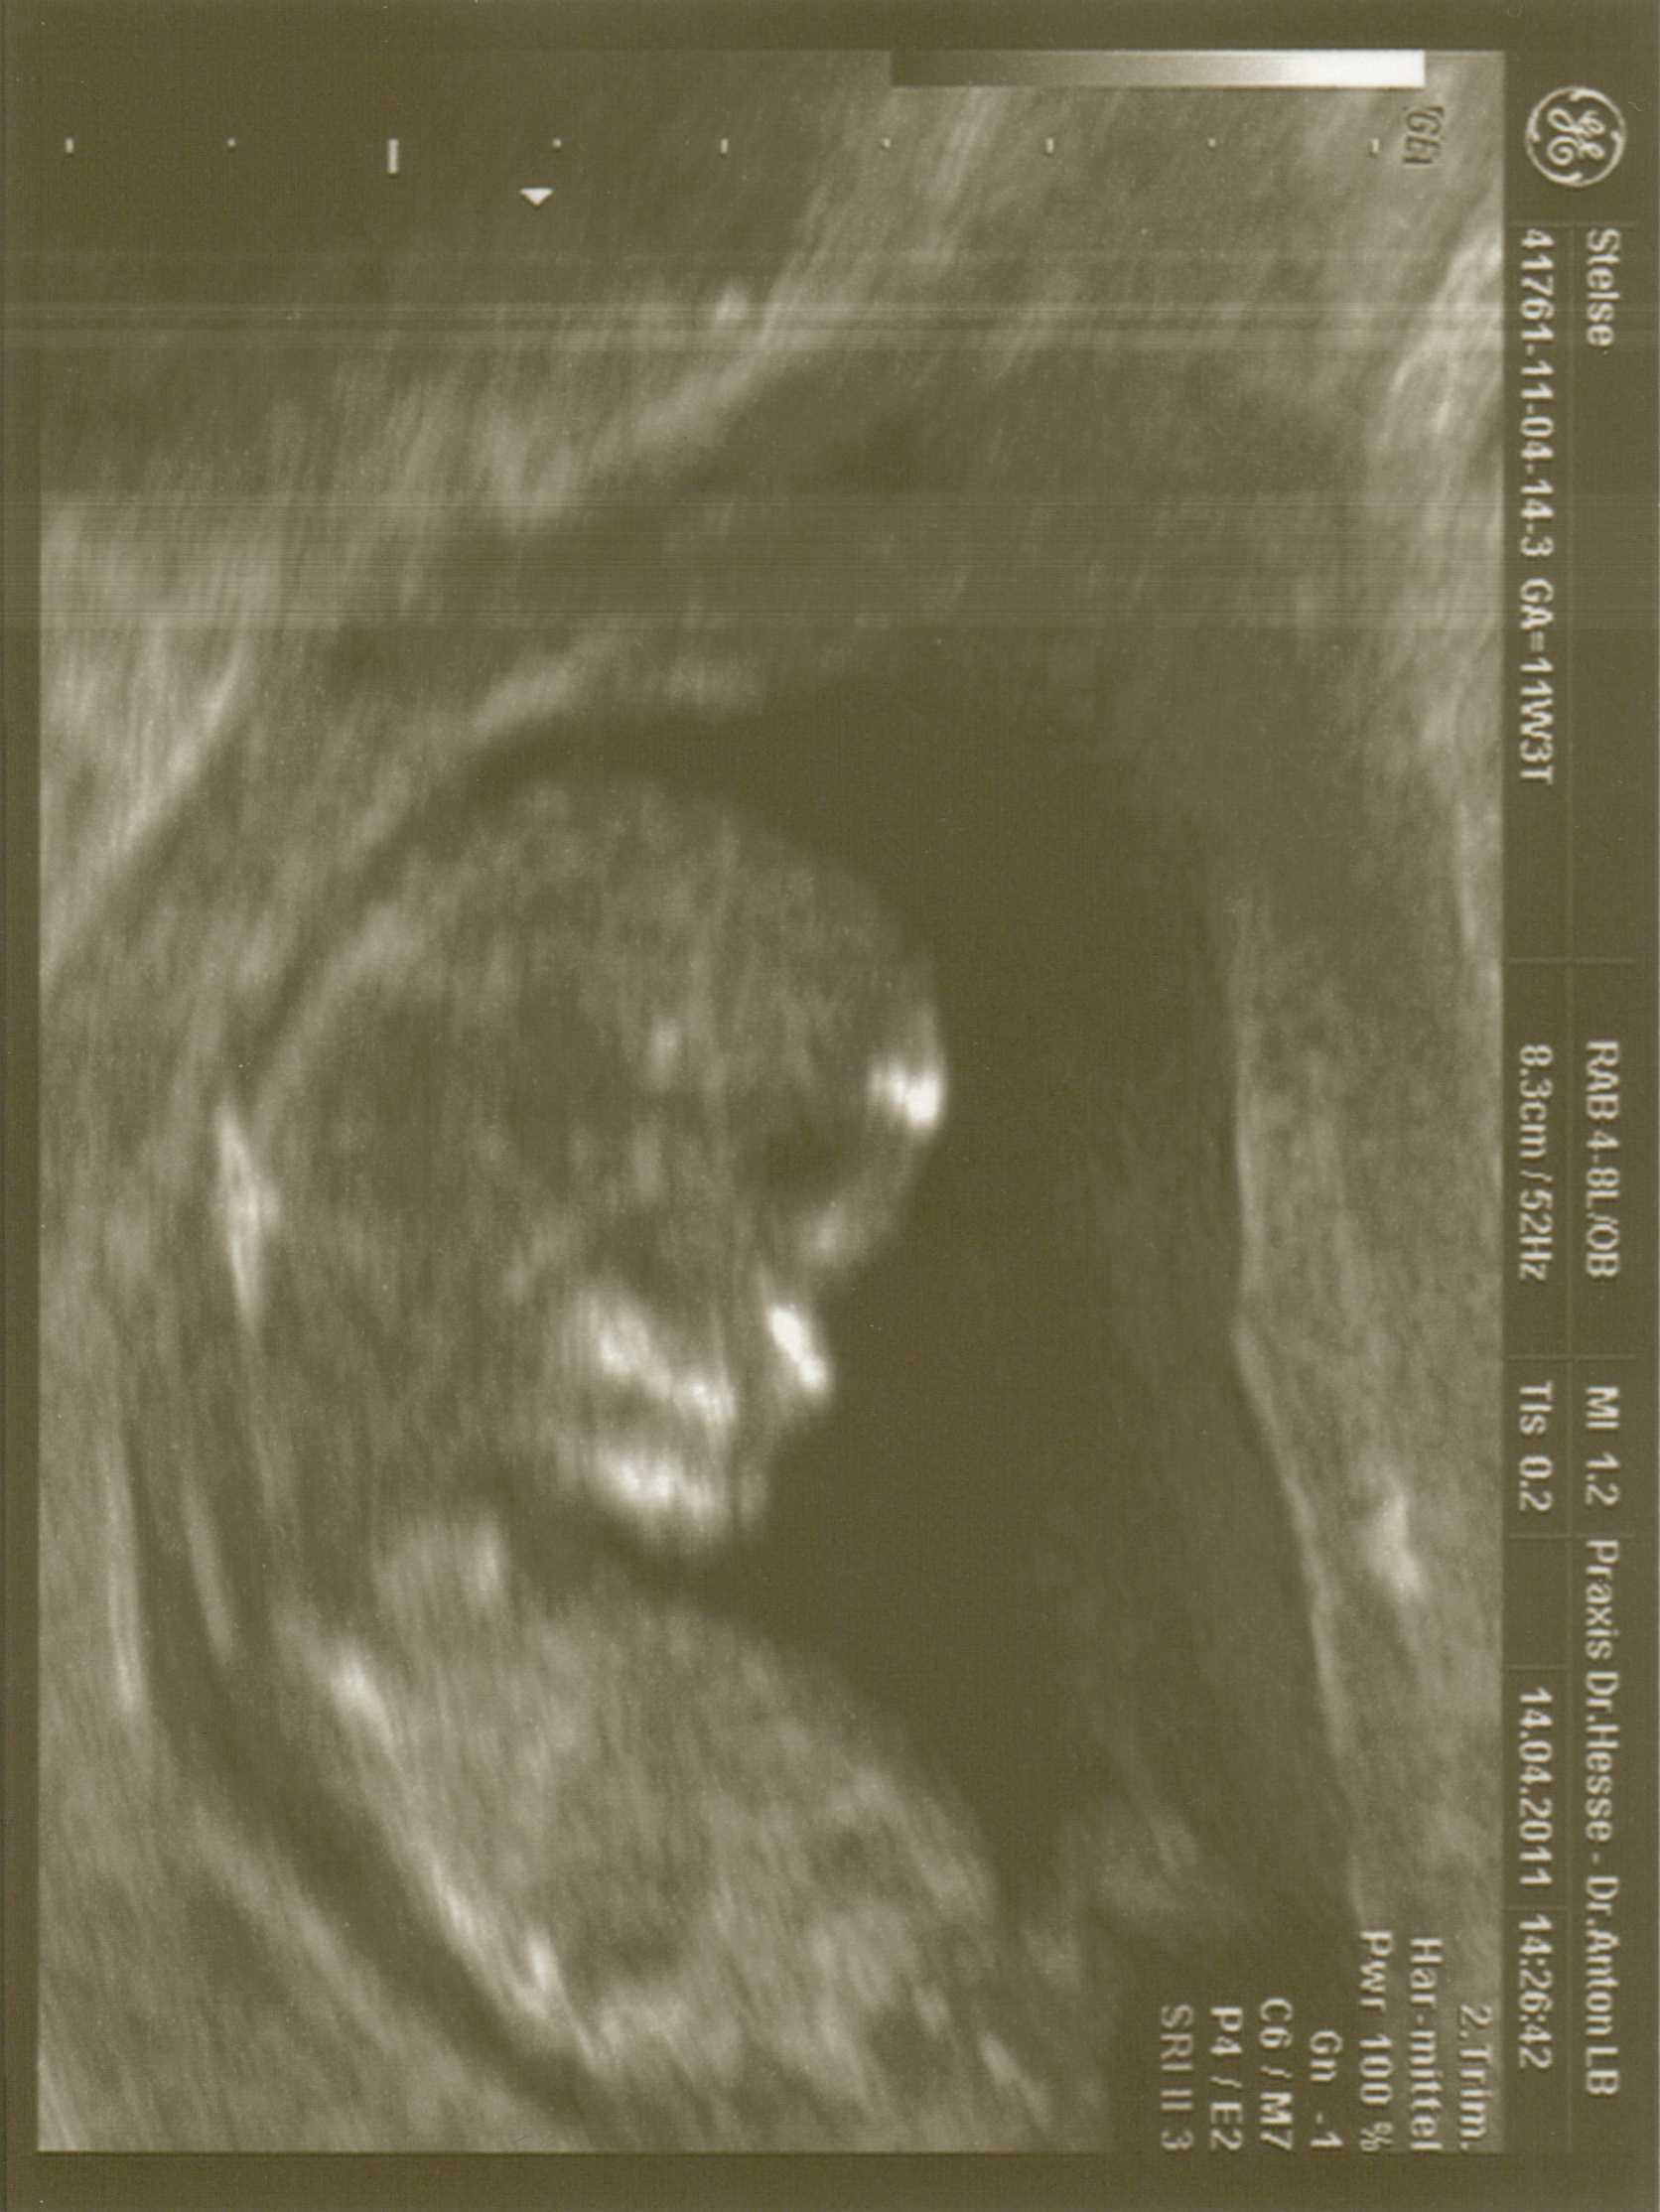

Da kann man ja wirklich alles erkennen. Wow. Ich hatte nicht damit gerechnet, sondern mit einem Foto, wie man sie üblicherweise beim Gyn sieht und ich nix erkenne, trotz Erklärungen.

Schickes Kerlchen (soll neutral sein!!!)

Isabell: So ein schönes Bild. *träum*

@bienchen und Dorie:Von mal zu Mal kann man auf den Bilder mehr sehen ud mein Gyn erklärt mir auch jedes mal alles geduldig.Lange wird der Krümel nicht mehr als ganzes zu sehen sein dann bekommt man nur noch Körperteile zu sehen.Wir wollen auf alle Fälle mal noch beim Gyn einen 3d Ultraschall machen lassen.Um die 20-22 Woche werden wir dann noch einen langen Ultraschall haben dann gehts zur Feindiagnostik.